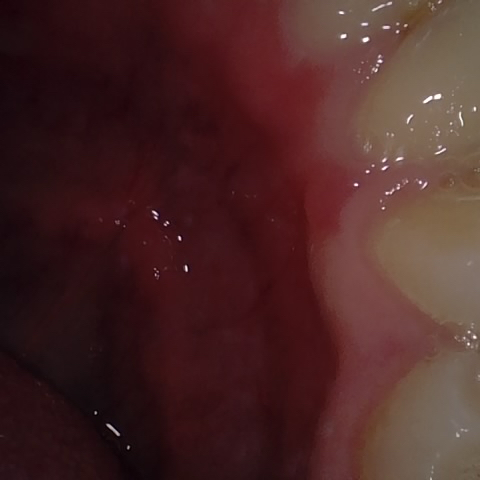

NHD20794

Annotated as "Good"